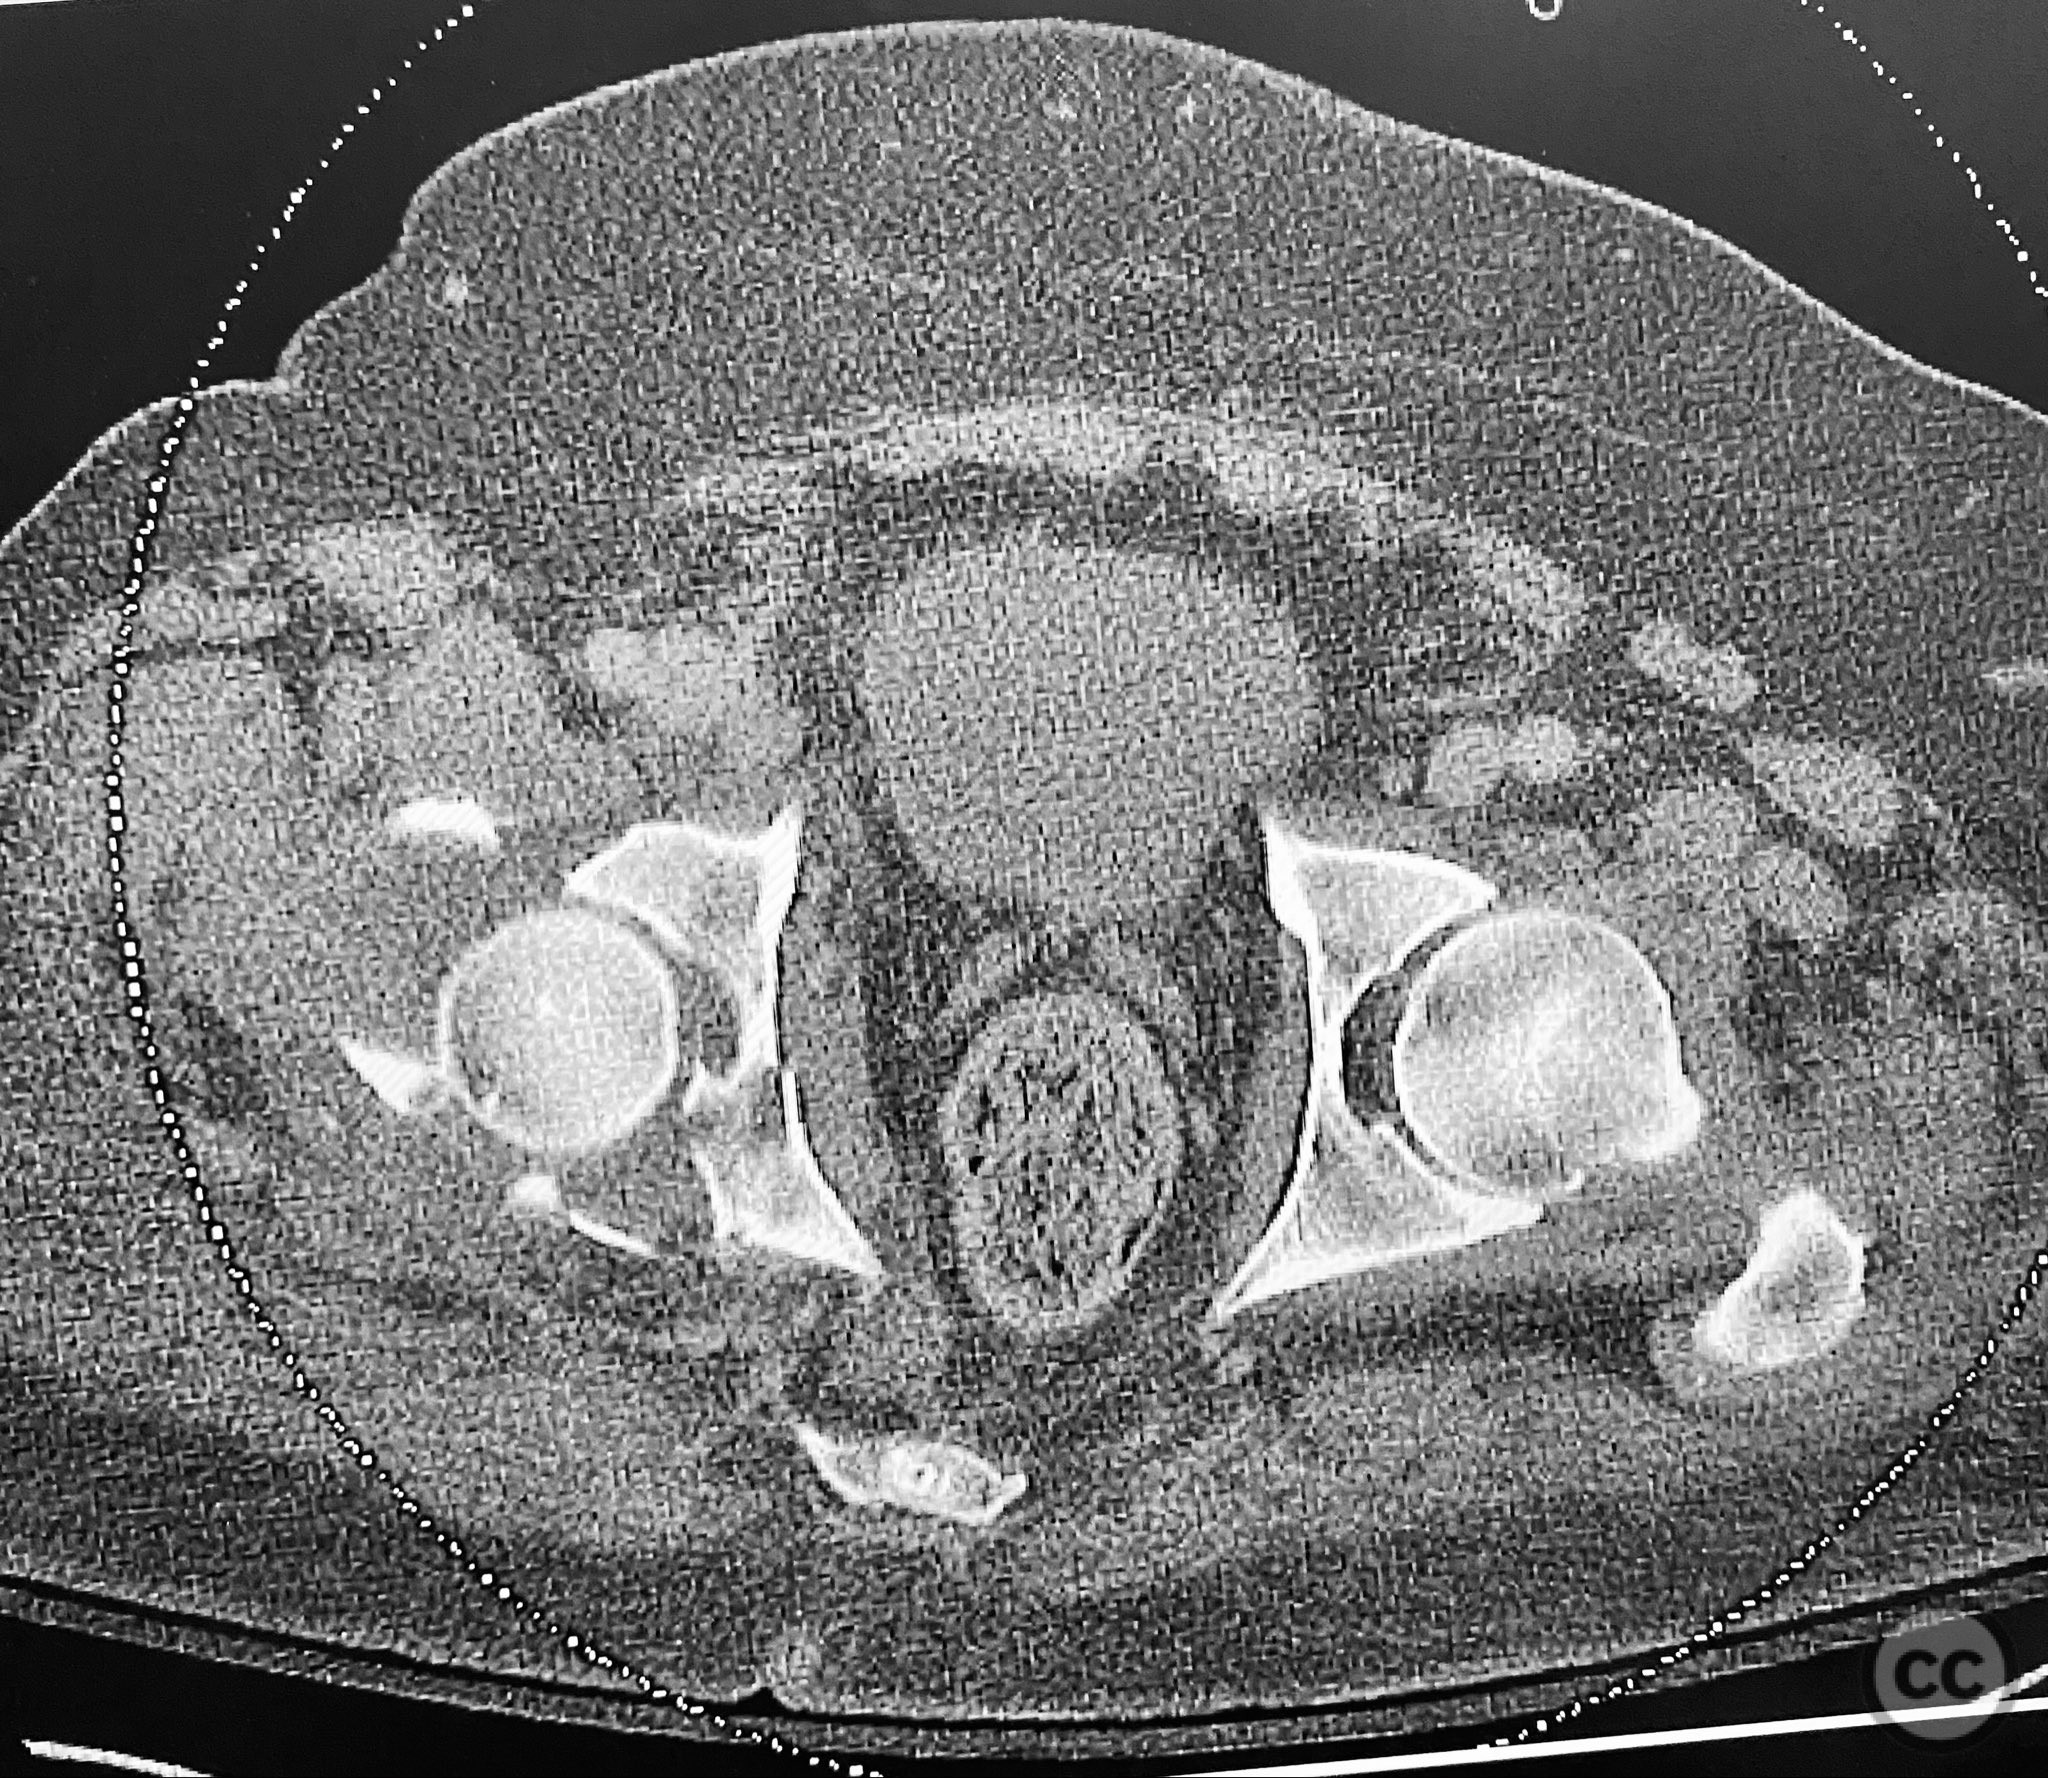

Clinical Details

Clinical and radiological findings:  A 79-year-old male sustained a high-energy injury in a motor vehicle collision, resulting in a complex acetabular fracture-dislocation. Radiographs and computed tomography demonstrated a posterior wall and transverse acetabular fracture (AO/OTA 62-B1.3), with the posterior wall fragments displaying an atypical caudal hinge configuration. The medial wall fragment was non-articular. Axial imaging revealed an impacted osteochondral fragment obstructing reduction, as well as disruption of the capsular structures adjacent to the intact articular segment. The obturator internus tendon appeared taut but intact, with no evidence of sciatic nerve impingement or superior gluteal neurovascular compromise.